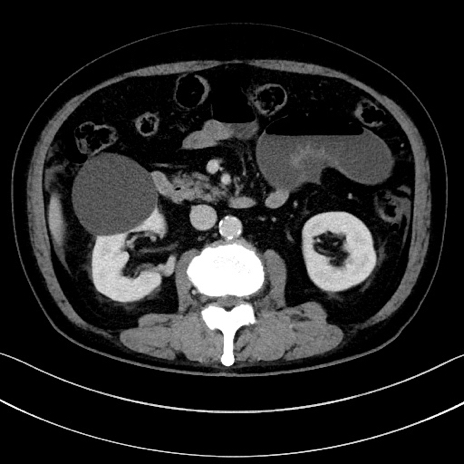

症例15(横断像)

【症例】70歳代男性

【主訴】腹痛

【現病歴】今朝から腹痛あり。全体的に痛い。特に左上の方。排ガスが今日はない。冷や汗が出る。

【既往歴】直腸癌術後

【身体所見】左側腹部〜上腹部に圧痛あり。腹膜刺激症状明らかなではない。軽度反跳痛。左下腹部に術後瘢痕あり。

【データ】WBC 7700、CRP 0.02